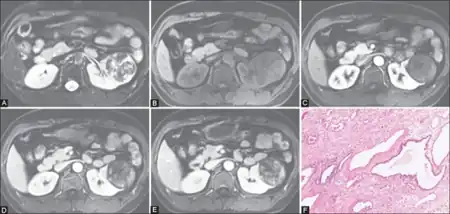

| Congenital mesoblastic nephroma, classic type, with typical features.[1] H&E stain. | |

- 1) The classic type occurs in ~39% of patients. Its tissues show interlaced spindle-shaped smooth muscle cells evidencing low mitotic activity with no evidence of tumor encapsulation; and infiltration into and entrapment of normal kidney tissue.[2]

- 2) The cellular type occurs in ~42% of patients.[2] Its tissues show densely packed fibrosarcoma-like cells evidencing high rates of mitosis, less infiltration of normal kidney tissue, and multiple areas of hemorrhage and cysts.[2][4]

- 3) The mixed type occurs in ~19% of patients. It shows a mixture of the classic and cellular types in different areas of the neoplasm.[2]